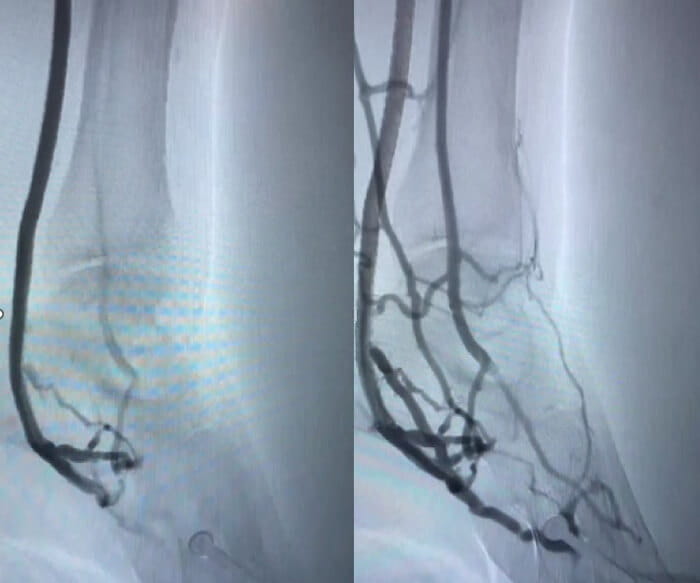

The PROMISE II U.S. pivotal clinical trial found that minimally invasive LimFlow therapy enabled most patients to avoid amputation and experience wound healing. The procedure is designed to bypass blocked arteries in the leg and rush blood back into the foot through the veins.

In the paper entitled “Transcatheter Arterialization of the Deep Veins in Chronic Limb-Threatening Ischemia: The PROMISE II Multicenter Prospective Study,” investigators evaluated 105 CLTI patients who were treated with transcatheter arterialization of the deep veins (TADV) using the LimFlow therapy. All patients were facing inevitable amputation before the procedure. At six months post-procedure, 76 percent of patients were able to keep their leg (also called limb salvage). Within the same time period, 76 percent of patients had completely healed or healing wounds. Freedom from all-cause mortality was 87 percent at six months.